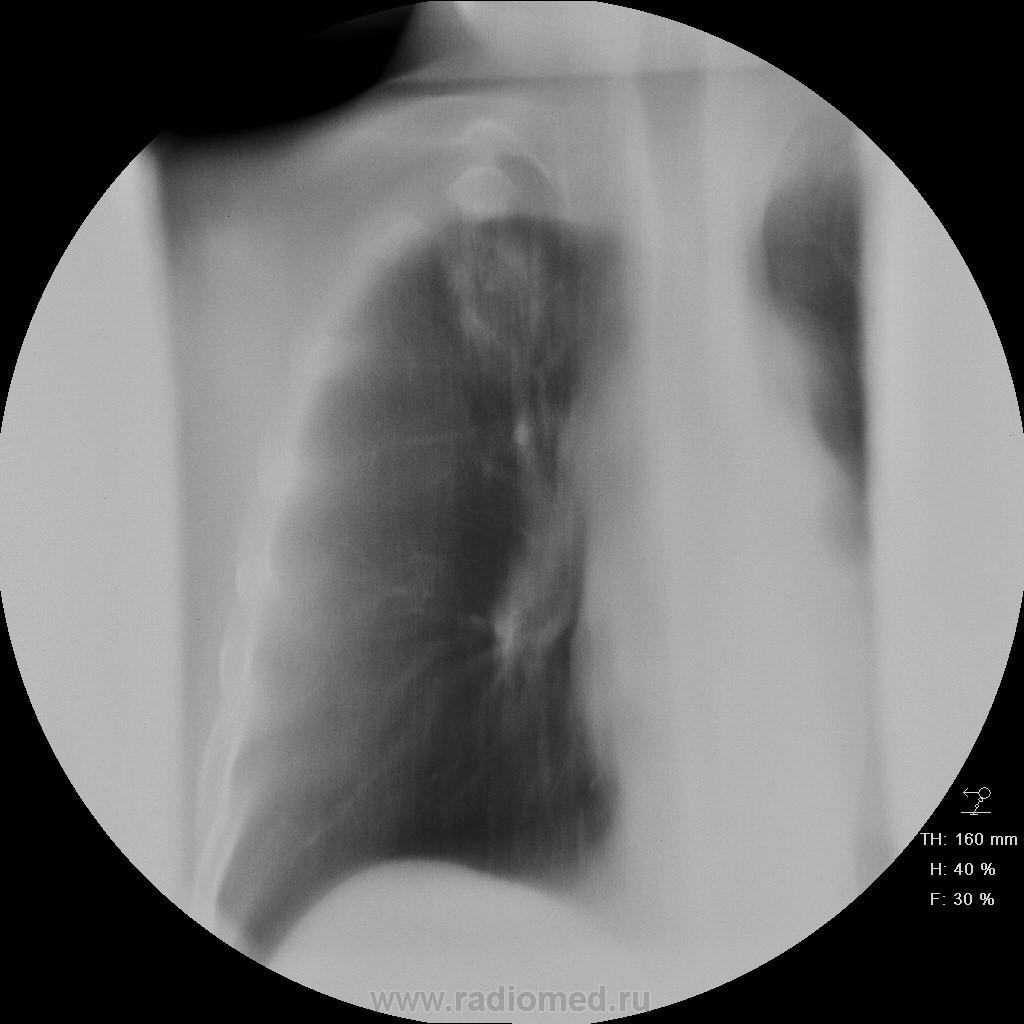

Пациет 60 лет после перенесения ОНМК. жалоб нет ( по легким) . СОЭ, лейкоциты, HB в норме.

Какие будут мнения.

КТ еще не запущен - так что выжимаем все из линейки...

Туберкулез под (?)

У больных с последствиями ОНМК следует думать об аспирационном генезе заболевания. В пользу этого свидетельствует поражение задних сегментов и двусторонняя локализация изменений.